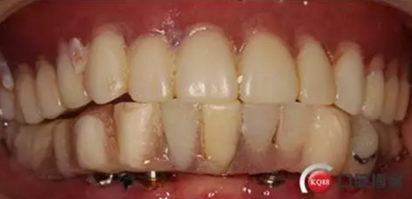

6)數(shù)字化義齒制作中心制作完成修復(fù)體臨時(shí)冠橋試戴,合適后完成最終二氧化鋯橋修復(fù)體

健康的牙齦袖口

戴牙:試戴,拍片確定邊緣密合后調(diào)整咬合,試戴一周后患者適應(yīng),咬合良好,基臺(tái)加力30N.CM,粘接劑粘固,去除多余粘結(jié)劑,拍片確定有無(wú)粘接劑殘留,并進(jìn)一步微調(diào)咬合

微笑是最美的溝通語(yǔ)言,患者的滿(mǎn)意是我們的追求

6)6個(gè)月后復(fù)查,修復(fù)體密合性均良好,修復(fù)效果符合預(yù)期,醫(yī)囑患者做好口腔衛(wèi)生預(yù)防種植體周?chē)?/p>

結(jié)果:本病例在觀察期內(nèi),種植修復(fù)獲得了良好的美觀功能的穩(wěn)定性